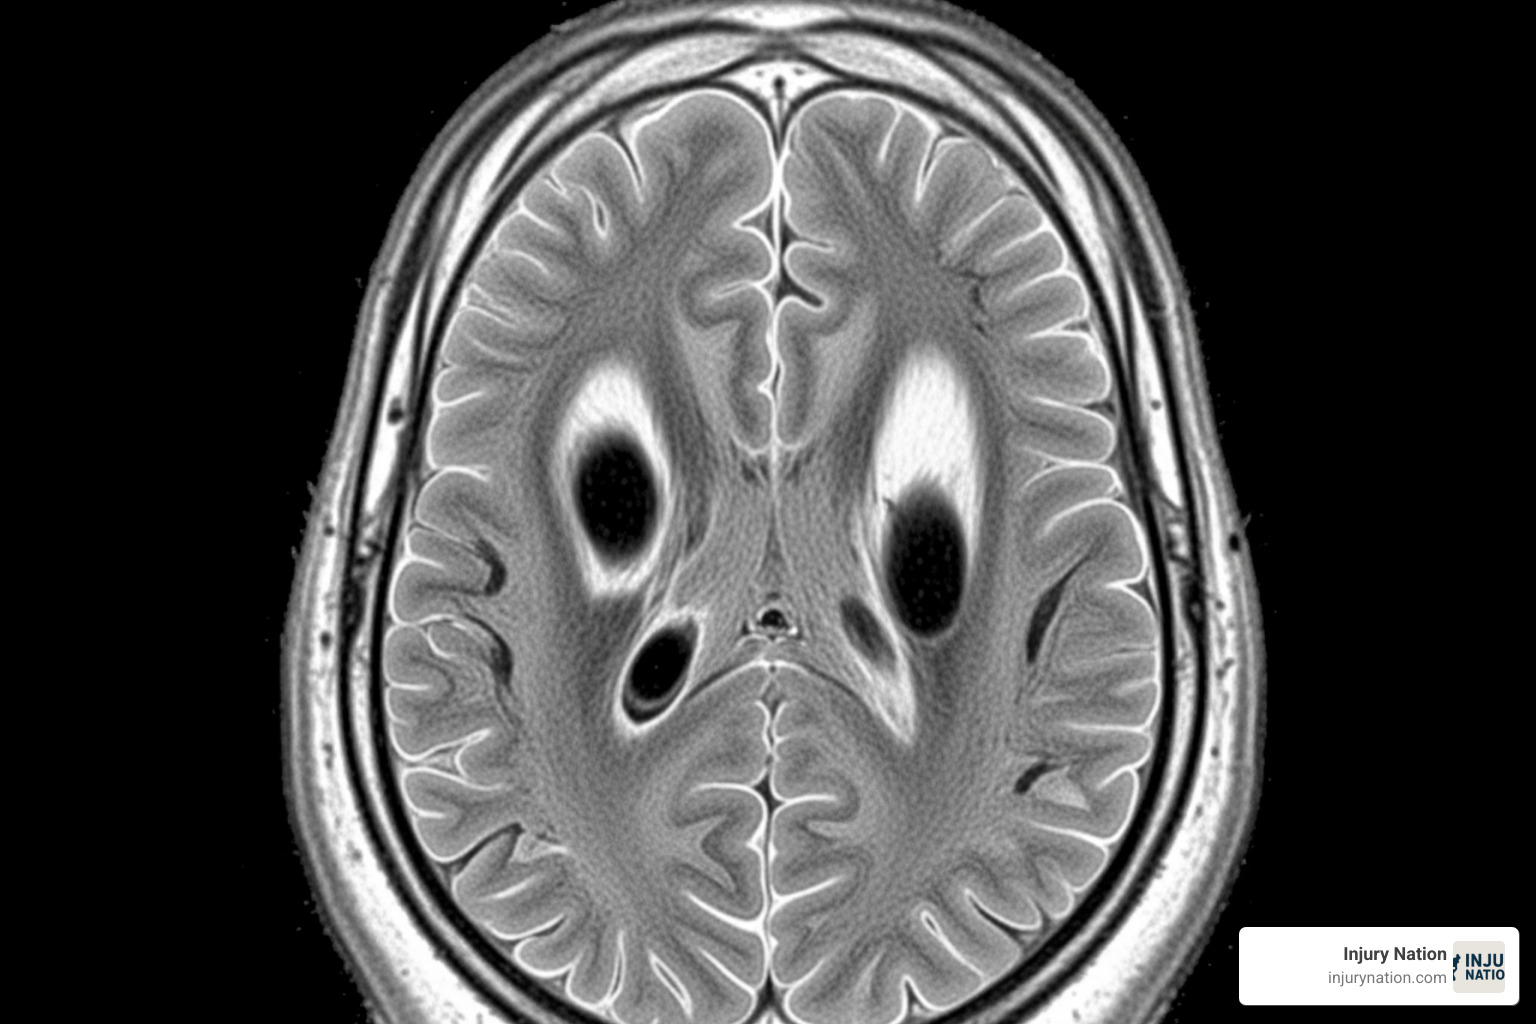

What is an Anoxic Brain Injury?

An anoxic brain injury occurs when the brain is completely deprived of oxygen. Because brain cells are highly sensitive to oxygen deprivation, they begin to die within about four minutes. This rapid cell death leads to lasting and debilitating brain damage.

The brain uses about 20% of the body’s oxygen, so when the supply is cut off, the damage is often irreversible and severe. A full recovery is rare, making this a devastating type of injury.